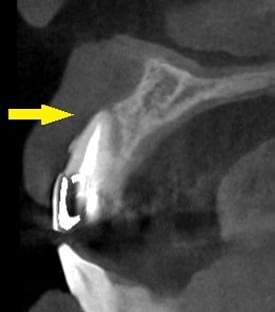

患者様のインプラント治療前のレントゲン写真です。右下顎大臼歯2本の抜歯後のレントゲン写真で、写真の黄色矢印は、歯の周囲の歯槽骨が大きく吸収されてしまっていました。

写真のように、CTで見ると、骨吸収の様子が良く分かり、下顎骨の中を通る神経近くまで骨がありませんでした。